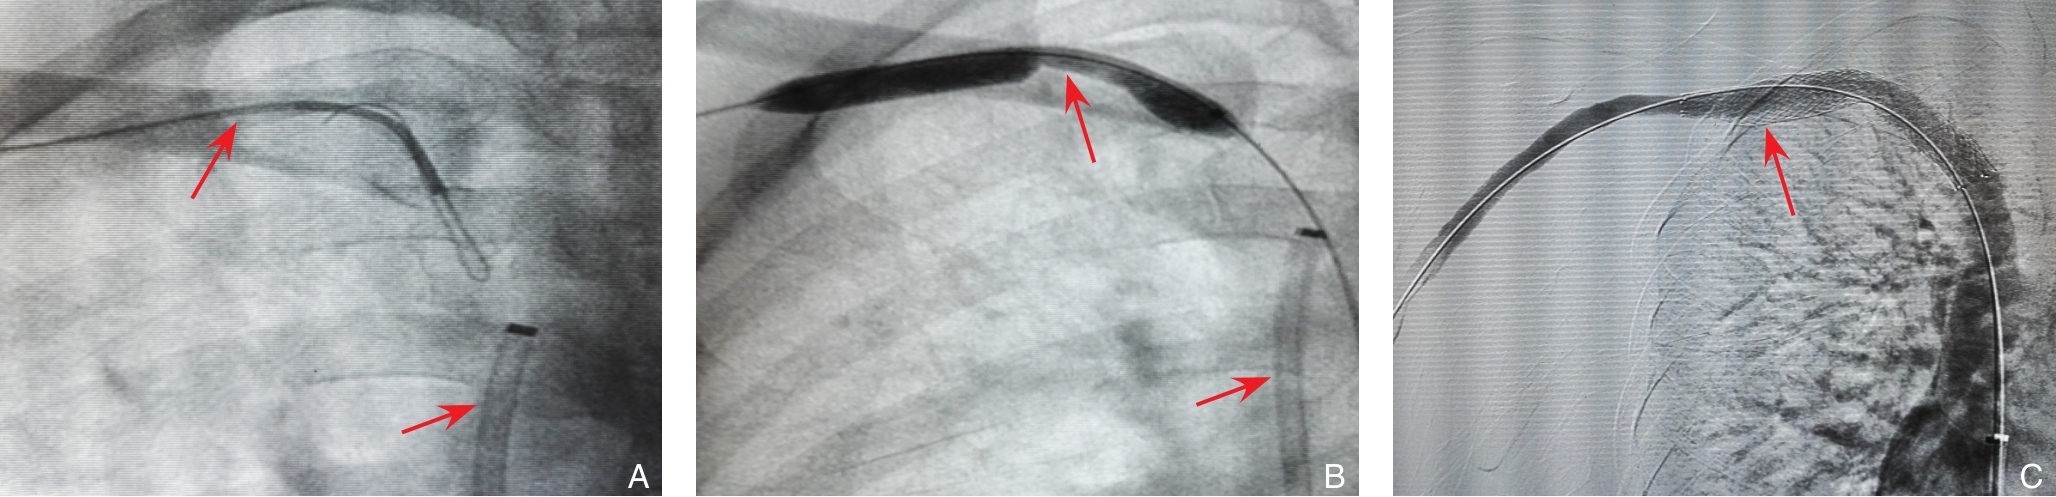

2025, 34(12):2664-2671. doi: 10.7659/j.issn.1005-6947.250617

摘要:背景与目的 中心静脉狭窄或闭塞(CVSO)影响血液透析疗效,但最佳静脉入路策略尚不明确。本研究比较单向静脉入路(UVA)与双向静脉入路(BVA)在维持性血液透析患者CVSO行经皮腔内血管成形术(PTA)或支架植入术(PTS)时的适用条件及技术成功率、临床成功率,并根据病变的位置和类型进行分层分析,旨在为不同病变制定个体化的静脉入路选择标准。方法 回顾性分析2019年7月—2024年2月赣南医科大学第一附属医院及南昌大学第二附属医院63例维持性血液透析CVSO患者的临床资料,其中UVA组37例、BVA组26例。比较不同静脉入路在CVSO介入治疗中的技术成功率(残余狭窄<30%)、临床成功率(症状缓解)及通畅率。结果 两组患者基线特征差异无统计学意义(均P>0.05)。总体技术成功率与临床成功率在UVA组与BVA组之间差异均无统计学意义(均P>0.05)。亚组分析显示,UVA组在上腔静脉及头臂静脉狭窄中的技术成功率高于BVA组,且UVA组在头臂静脉狭窄中的临床成功率高于BVA组;而在锁骨下静脉闭塞中,BVA的技术成功率及临床成功率均优于UVA(均P<0.05)。两组6个月及12个月一期、二期通畅率差异均无统计学意义(均P>0.05)。结论 对于上腔静脉或头臂静脉狭窄,优先采用UVA可获得较高的成功率;而在锁骨下静脉闭塞的介入治疗中,BVA更具优势。基于病变部位和类型合理选择静脉入路,有助于提高CVSO介入治疗的成功率并降低操作难度。